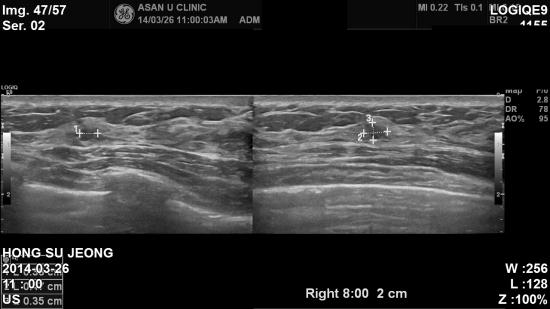

좌측유두에서 피가나와 내원하신 36세 여성분이십니다.

본원 초음파검사상 의심되는

좌측

2곳과

우측

2곳을

조직검사시행하였고

,

좌측은 비정형유관증식증,

우측은 상피내암으로

진단되었습니다

.